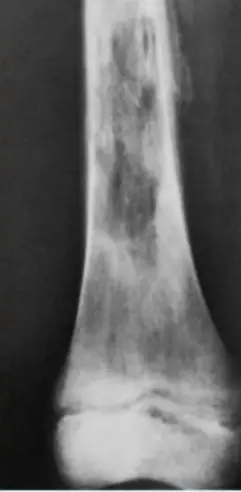

Tibial Fractures

Tibia and Fibula Fracture

Diagnosis: Segmental and comminuted fracture of tibia and fibula